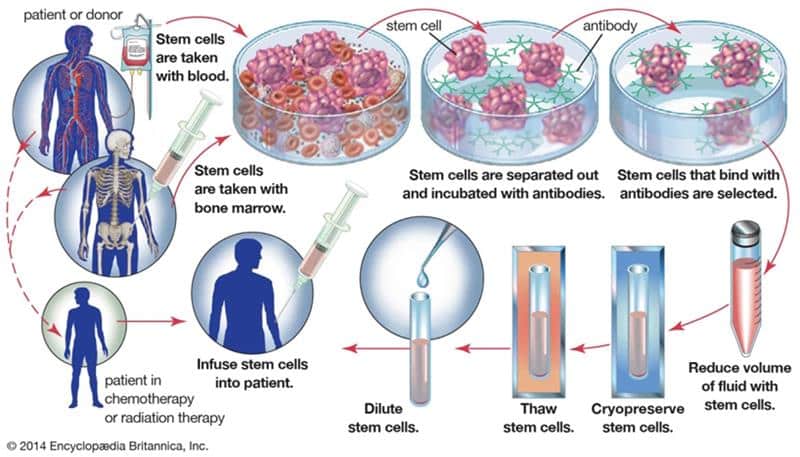

Role of the Nurse in Bone Marrow Transplantation

Bone marrow is a vital element of the human body that produces blood cells. It includes stem cells capable of...Read More